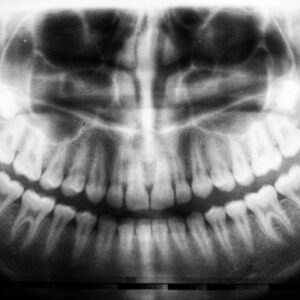

Photo Dental X-ray